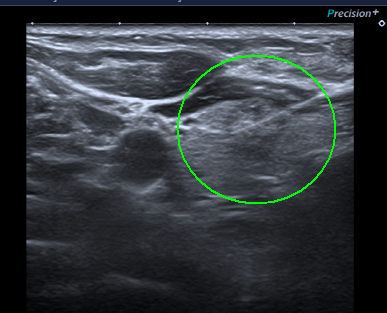

양성 결절로 진단된 증례 3

양성결절로 의심되는 소견이나 최근 커진 느낌(전경부의 불편함, 목의 이물감)이 있어 세포흡인검사를 실시하여 양성소견을 통해 확인하였습니다.